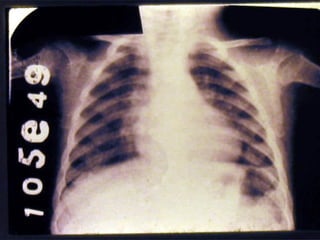

2. Signos Circunstanciales No se encuentran siempre, sino que están condicionados a causas ambientales o ecológicas, no específicas: alteraciones de la piel y faneras, lesiones oculares, de lengua, óseas, de músculos y ligamentos, de aparato digestivo, alteraciones hematológicas, neurológicas, edema

2. Signos CircunstancialesNo se encuentran siempre, sino que están condicionados a causas ambientales o ecológicas, no específicas: alteraciones de la piel y faneras, lesiones oculares, de lengua, óseas, de músculos y ligamentos, de aparato digestivo, alteraciones hematológicas, neurológicas, edema